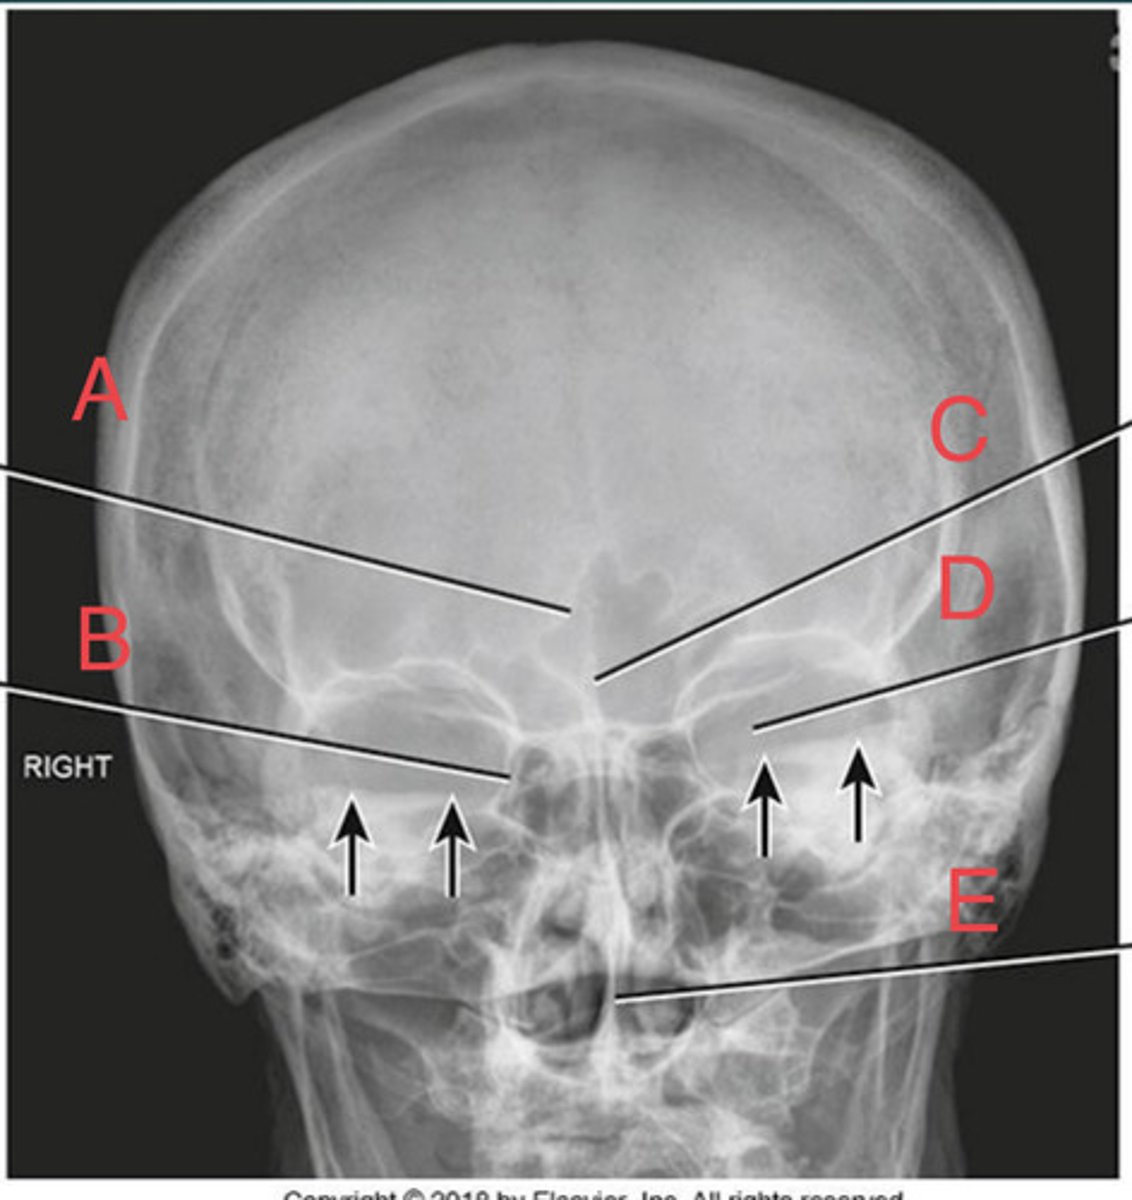

PA Caldwell Sinuses

What position?

frontal sinus of the frontal bone

A.

R. ethmoid sinus of the ethmoid bone

B.

crista galli of ethmoid bone

C.

L superior orbital fissure of the sphenoid

D.